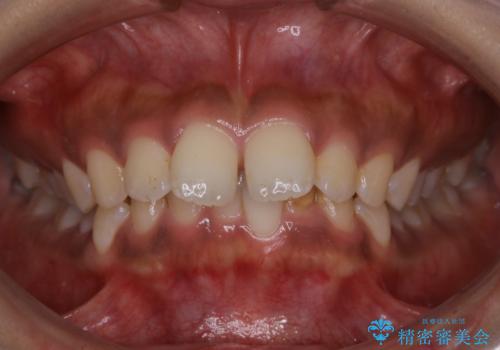

![[ マウスピース矯正 ] 前歯の角度・がたつきを治したい。の症例 治療前](https://seimitsushinbi.jp/wp/wp-content/uploads/2024/02/IMG_7820-500x350.jpg?v=1707810350)